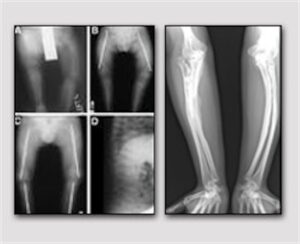

Osteogenesi imperfetta: nuove ricerche

Si chiama O.I. In Motion, Osteogenesi Imperfetta in Movimento, e già il titolo di questo Topical Meeting medico internazionale, a...